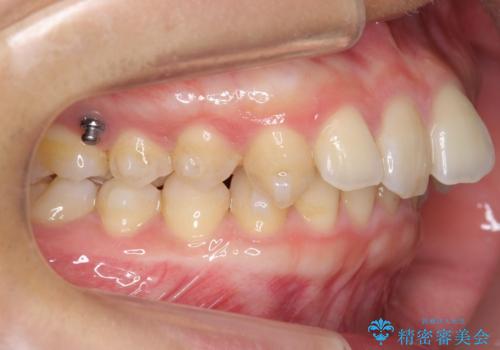

時間はかかりますが非抜歯で治療することにして、インビザライン矯正とワイヤー矯正を交互に行い仕上げました。

インビザライン矯正だけでなく、途中ワイヤー矯正もはさみました。前歯のかみ合わせが深く、本当に大変な治療でしたが協力度も高く非抜歯で上の奥歯を後ろに動かすことができました。